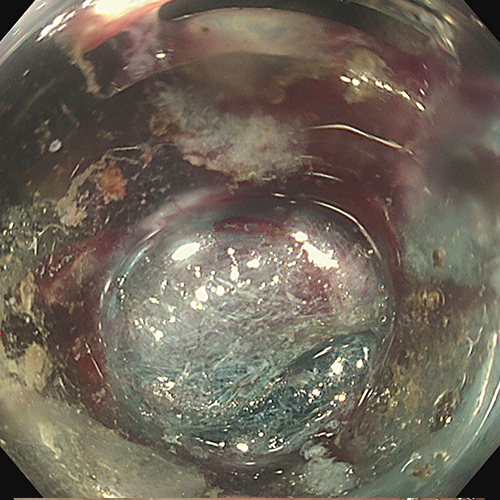

Dr Sergio Coda removed the lesion en bloc using Speedboat UltraSlim, leaving a clean muscle bed.